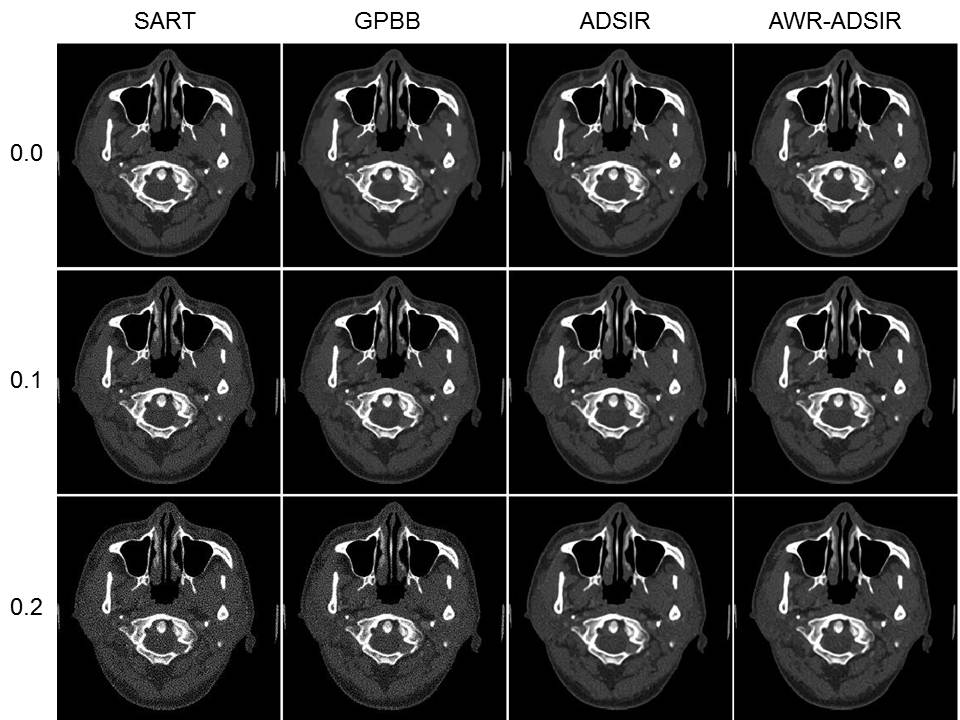

图2. 字典学习重建算法与对比算法重建结果比较。第四列是本文提出的算法重建结果,一到三列为对比算法,分别为SART算法、GPBB算法以及经验选取正则化参数的传统字典学习算法。第一到三行分别为无噪声投影数据以及加入0.1%、0.2%高斯噪声的投影数据的重建结果。由该图可以看到,本文提出的算法重建图像的空间分辨率和图像质量高于SART和GPBB算法,与传统字典学习算法相当,说明正则化参数选取模型的准确性以及字典学习重建算法的优越性。